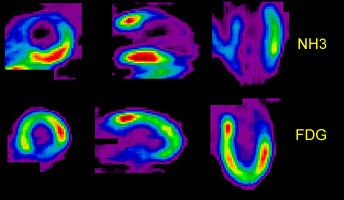

Perfusion-Metabolism Mismatch: The case below is from a 62-year-old female patient 8-years status post CABG and 6 months following an anterior wall myocardial infarction. The patient presented with symptoms of congestive heart failure and a LV ejection fraction of 22%. Perfusion exam was performed using NH3. There is an extensive, severe perfusion defect involving the apex, anterior, and septal walls. Metabolic images performed using FDG demonstrate disproportionately enhanced uptake when compared to the perfusion study. This is referred to as a perfusion-metabolism mismatch which is considered reflective of hibernating myocardium. At angiography the patient was found to have an occluded bypass graft and a second bypass was performed. Six months later the patient was asymptomatic and the LV ejection fraction had increased to 47%. Case courtesy of CTI, Inc. |